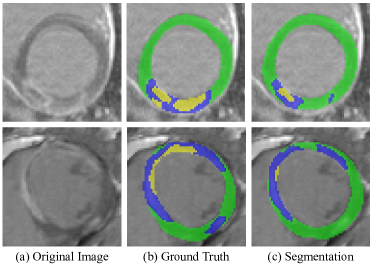

One of the important tasks is to segment the myocardium into different regions, including normal myocardium, infarction, and no-reflow from multi-sequence CMR dataset. Manual annotation is generally time-consuming, tedious and subjects to inter- and intra-observer variations. Thus, a fully automatic segmentation method is highly desired in clinical practice. Figure 1 presents some images from different myocardial infraction cases and the corresponding left ventricle, healthy myocardium, infraction, and no-reflow annotations. It can be observed that the intensity appearances vary significantly among different cases, and both infraction and no-reflow areas have ambiguous boundaries and low contrast. Thus, it is very challenging to automatically segment them.

Refer to caption

Figure 1: Visual examples of different myocardial infraction delayed-enhancement cardiac MR images. The 1st row and the 2nd row are the original image and ground truth, respectively. In the 2nd row, the red, green, blue,and yellow color denote left ventricle, healthy myocardium, infraction, and no-reflow, respectively.